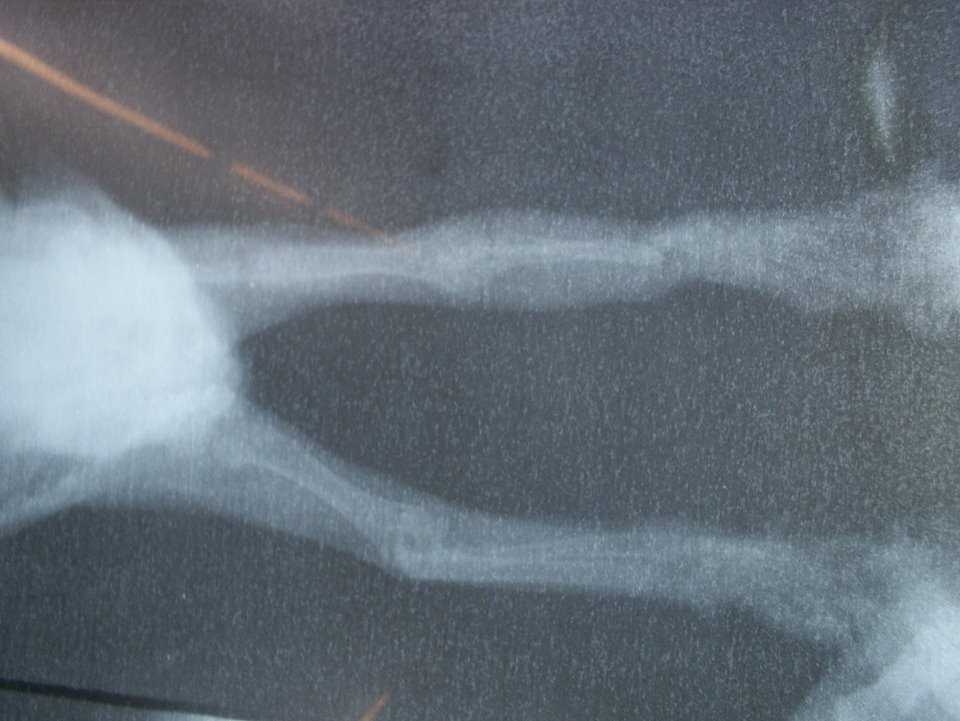

主題: 右前腳被捕獸夾夾斷之小黑貓 申請者姓名: 許桂菱 花色: 申請日期: 2013-12-11 00:29:38 申請者部落格: 申請者臉書網址: 所在縣市/合作醫院: 彰化縣/成愛動物醫院 治療費用: 6200元 需求人數: 8人 已結案 (2014-01-10 17:49:01) 報名人員: tiffany、劉定惠、Justin Wang(已付款)、Tiffany Shen(已付款)、小月(已付款)、shirina(已付款)、徐芳芳(已付款)、Chen-Pang Chang、Captainken Lai(已付款)、詩詩(已付款)、潼潼(已付款)、 候補人員: 牛豬魚、 動物病情說明: 鹿港貓友於下班時聽到小貓哀叫聲,尋找叫聲發現其公司後門旁的私人雜物間有隻小黑貓被捕獸夾夾傷,故緊急向志工求救,志工無法立即趕至現場,請貓友先抓至合作之動物醫院緊急處理,經照X光後右前腳夾扁,醫生施作打釘接連固定,因傷了神經前腳掌沒有反應且無法正翻,小貓目前也只有兩個月大,需持續觀察未來是否需要截肢!

狂犬疫苗費用由志工負擔動物近況說明: 由發現的貓友帶回照料,已尋求中醫針灸但醫生認為沒有幫助,故需等待小黑貓再大一點觀察扁骨連接生長情況才能再評估!